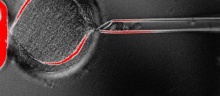

> Primeiro clone de embriões humanos

Dezesseis anos depois da clonagem do primeiro mamífero, a ovelha Dolly, cientistas conseguiram clonar um embrião humano em seus primeiros estágios de desenvolvimento. Os protoembriões foram usados para produzir células-tronco embrionárias capazes de se transformar em qualquer tecido do corpo e que poderão ser usadas para o tratamento de lesões e doenças graves como Parkinson, esclerose múltipla e problemas cardíacos.